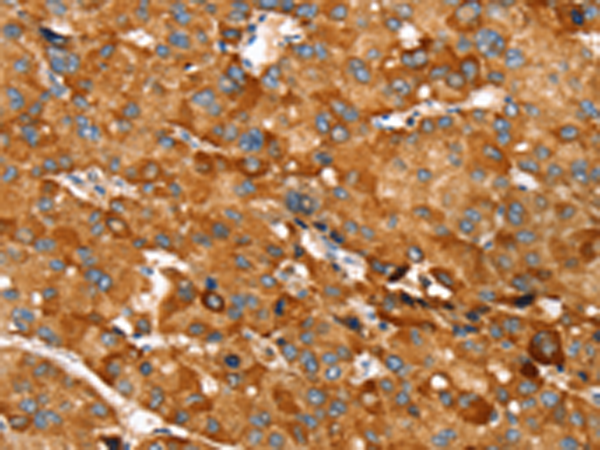

分类: 科研抗体货号: P08701别名: RAI; RNH应用: WB,IHC反应种属: Human